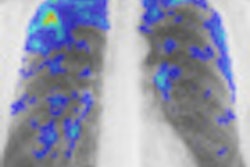

Current British border policies require immigrants from countries with a TB incidence higher than 40 per 100,000 people to have a chest x-ray on arrival to check for active TB.

To see whether the screening was effective, British researchers analyzed demographic and test result data from 2008 to 2010 at three immigrant screening centers in Britain using a highly specific blood test for detecting latent tuberculosis, called an interferon-gamma release assay (IGRA).

Their results, published in the Lancet Infectious Diseases journal, showed 20% of recent immigrants from the Indian subcontinent and almost 30% from sub-Saharan Africa are carriers of latent TB.

This means the current screening policy, which excludes immigrants from the Indian subcontinent, has been missing 70% of imported latent TB, they said.